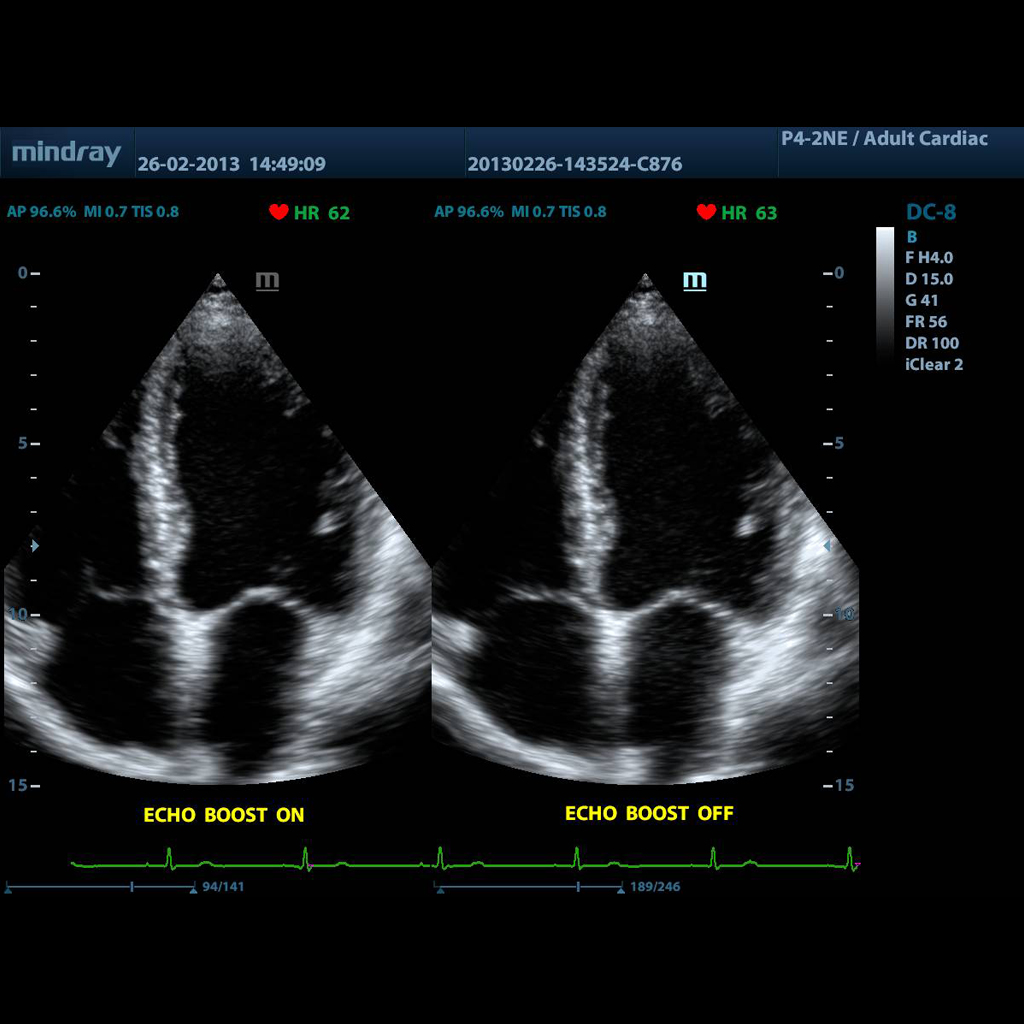

Уникалната технология на Mindray за адаптивна обработка на сигнала с интелигентно ехо-разпознаване. Подобрява хомогенността на изображенията в цялото видимо поле, предназначена да използва съотношението естествен информационен сигнал / шум за подобряване на слабите ехо сигнали, като същевременно потиска фоновия шум, осигурявайки по -балансирано, осветено и интензивно изображение; подобрява зрението на тъканните слоеве на миокарда. Подобрява хомогенността на изображенията в цялото видимо поле. Основни функции:

• използва съотношението сигнал-шум

• усилване на слабите ехо сигнали, като същевременно потиска околния шум

• осигурява балансирана яркост на изображението

• по-добра контрастна разделителна способност на миокарда

• по-добър контрол на шума в камерите и мускулите